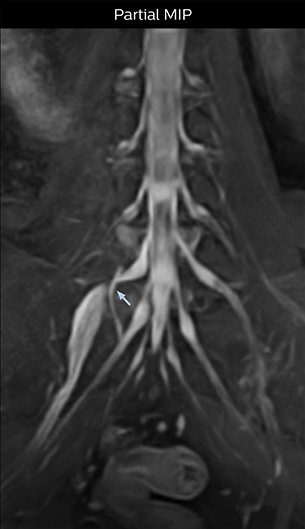

“In such case, we would then browse through axial T2-weighted MR images slice by slice and mentally reconstruct the actual situation based on both radiculography and MRI. Fortunately, NerveVIEW can now very well show nerve courses and presence of nerve compression or edema in one single image series.” “We have often seen NerveVIEW directly depict details of the nerve compression that were not observed by radiculography. Therefore, we think that with NerveVIEW we can reduce the number of invasive examinations, especially for some patients with lumbar plexus symptoms.”

The key concept in MR neurography, Dr. Yabuki stresses, is the ability to directly visualize spinal nerves, versus inferring the presence of pathology indirectly. “Before NerveVIEW, we estimated compression of the nerve by looking for the presence or absence of fat signal on other MR images,” he says.

“For example, in sagittal images, when the presence of fat is observed in the intervertebral foramen, it suggests that there is a margin around the nerve. Similarly, the absence of fat indicates that the nerve is being compressed. So, we used to deduce nerve compression indirectly. With NerveVIEW, however, we can observe the condition of the nerves directly, regardless of the presence or absence of fat. We always prefer such direct observation of anatomy over having to make an inference about it.”

“Although symptoms of typical disc herniation and atypical hernia are very similar, the actual site of herniation is different. It is therefore important to characterize the nerve’s condition both inside and outside of the intervertebral foramina. “Conversely, if we see no abnormality in NerveVIEW, we can assume at least that there is no severe condition that requires surgery. Like this, it can help us avoid unnecessary surgery. NerveVIEW can have a tremendous impact in this way.”

“NerveVIEW can clearly show nerve courses and presence of nerve compression. However, when multiple abnormalities are seen, it can still be hard to determine which nerve is causing the symptoms,” says Dr. Yabuki. “In our experience so far, we see abnormal findings on NerveVIEW in about 70% of elderly patients. As the pain is usually caused by only one nerve, we thus need to find the exact corresponding nerve.” “With a nerve root block, the patient's pain is improved by infiltration of local anesthesia directly around the nerve root considered to be responsible. Knowing such nerve root block findings prior to image interpretation, helps to easily recognize abnormal findings on NerveVIEW as well. In other words, without a priori knowledge, based on symptoms and/or nerve root block findings, we must be aware of the possibility of overdiagnosis.”

The addition of the nerve-selective NerveVIEW sequence to its spine MRI protocol has given NFMC competitive advantages, according to Tanji. “Since we started including NerveVIEW routinely, the demand for lumbar spine MRI examinations has increased, especially for pre-surgical planning purposes and for patients with chronic lower extremity symptoms,” he says. “Moreover, because no other hospitals in our region are doing nerve plexus imaging yet, we often receive referrals for MR neurography studies from other hospitals even if they have an MRI scanner. Some requests come from as far as 100 km away. NerveVIEW definitely provides us a competitive advantage.” “Based on our experience, we can certainly recommend NerveVIEW to other centers,” Dr. Yabuki adds. “The sequence opens up many possibilities to facilitate the diagnosis of lower extremity pain and to inform our decision-making regarding therapy and surgery.”